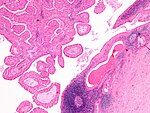

- Submandibular:

- Serous and mucinous glands.

- Serous ~90% of gland.

- Mucinous ~10% of gland.

- Serous demilunes = mucinous gland with "cap" consisting of a serous glandular component.

- Demilune = crescent.[3]

- Image: Serous demilunes (duke.edu).[4]